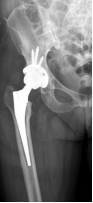

近日,一位久病缠身、下地活动极其困难的患者在我校附属南海医院做了人工全髋关节置换术,术后第二天患者就已下地站立、行走,且患肢短缩完全得到纠正,髋关节功能恢复良好。病人恢复如此迅速,出乎患者及其家属们的预料,该手术也成为3D打印在骨科和人工关节精准手术领域中的应用典范。

术后

以往在人工髋关节置换手术前,医生只能根据术前X线片去判断髋臼骨缺损的大小和位置,对手术的帮助非常有限。3D打印的关节模型,就能帮助医生术前精确的了解和测量髋臼缺损的大小和位置、同时了解整个骨性髋臼臼壁、臼底的骨质厚度,为手术提供精准的术前设计,合适的假体选择,大大缩短手术时间,减少了手术并发症的发生。3D打印技术不仅可以术前为患者定制个体化的手术方案,而且还可以运用模型在体外进行“实战演练”,确保了人工髋关节精准置换。同时也可应用于外科教学,具有直观、全面、准确、可交互的特点,有效地缩短年轻医生的手术学习曲线,提高手术的成功率。做到了精细、精准,提高了复杂人工关节置换术的成功率、降低高难度人工关节置换术的失败率,实现了骨科在复杂的关节置换术上又一次技术突破。通过与患者的术前交流和沟通,使患者充分地理解接受手术,积极配合医生术后康复锻炼。